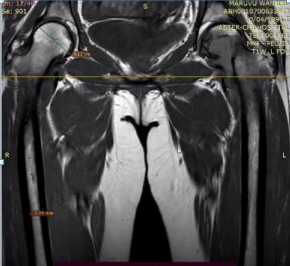

31 year old female presented to us with complaints of limp while walking from past few months. No history of fever, loss of appetite, weight loss or any other constitutional symptoms. Patient is a post operated case of Medulloblastoma brain and occipital craniotomy with VP shunting was done in May 2018 in London for the same along with adjuvant chemo-radiation. Patient received craniospinal radiotherapy (35Gy/21fractions) + (20Gy/12 fractions) for approx. 6 weeks in Aug-Sep 2018. Patient received 6 cycles of Cisplatin, Vincristine and Lomustine, during Sep 2018-Dec 2018. Patient was on regular follow up and regular MRI Brain was done during follow up and patient was asymptomatic during the time period of last 4 years, until last month when she developed sudden onset right lower limb limp while walking. Patient was evaluated for above mentioned complaints and relevant scans were done. On X ray (Fig. 1),   MRI (Fig. 2) and PET scan (Fig. 3) multiple lytic lesion were seen involving D7 vertebra, right ischium and left proximal femur. Left proximal femur lesion was measuring 5.5 x 3.8 x 3.2 cm with a cortical breach. CT guided biopsy from D7 vertebra was done which showed typical emperipolesis (Fig. 4) S/O Rosai Dorfman Disease. IHC was done and was positive for S100 and CD68 suggestive and negative for CD1a suggestive of Rosai Dorfman Disease. High risk of pathological fracture of left proximal femur (Mirel’s Score – 11) was explained to the patient and cemented bipolar hemiarthroplasty was done for left hip. Post op patient was mobilized on Day 1 and dressing was changed at Day 5 and patient was discharged at Day 6. Final histopathology impression was s/o Extranodal Rosai Dorfman disease.

Fig. 2 (a) MRI Coronal section                   (b) Axial Section